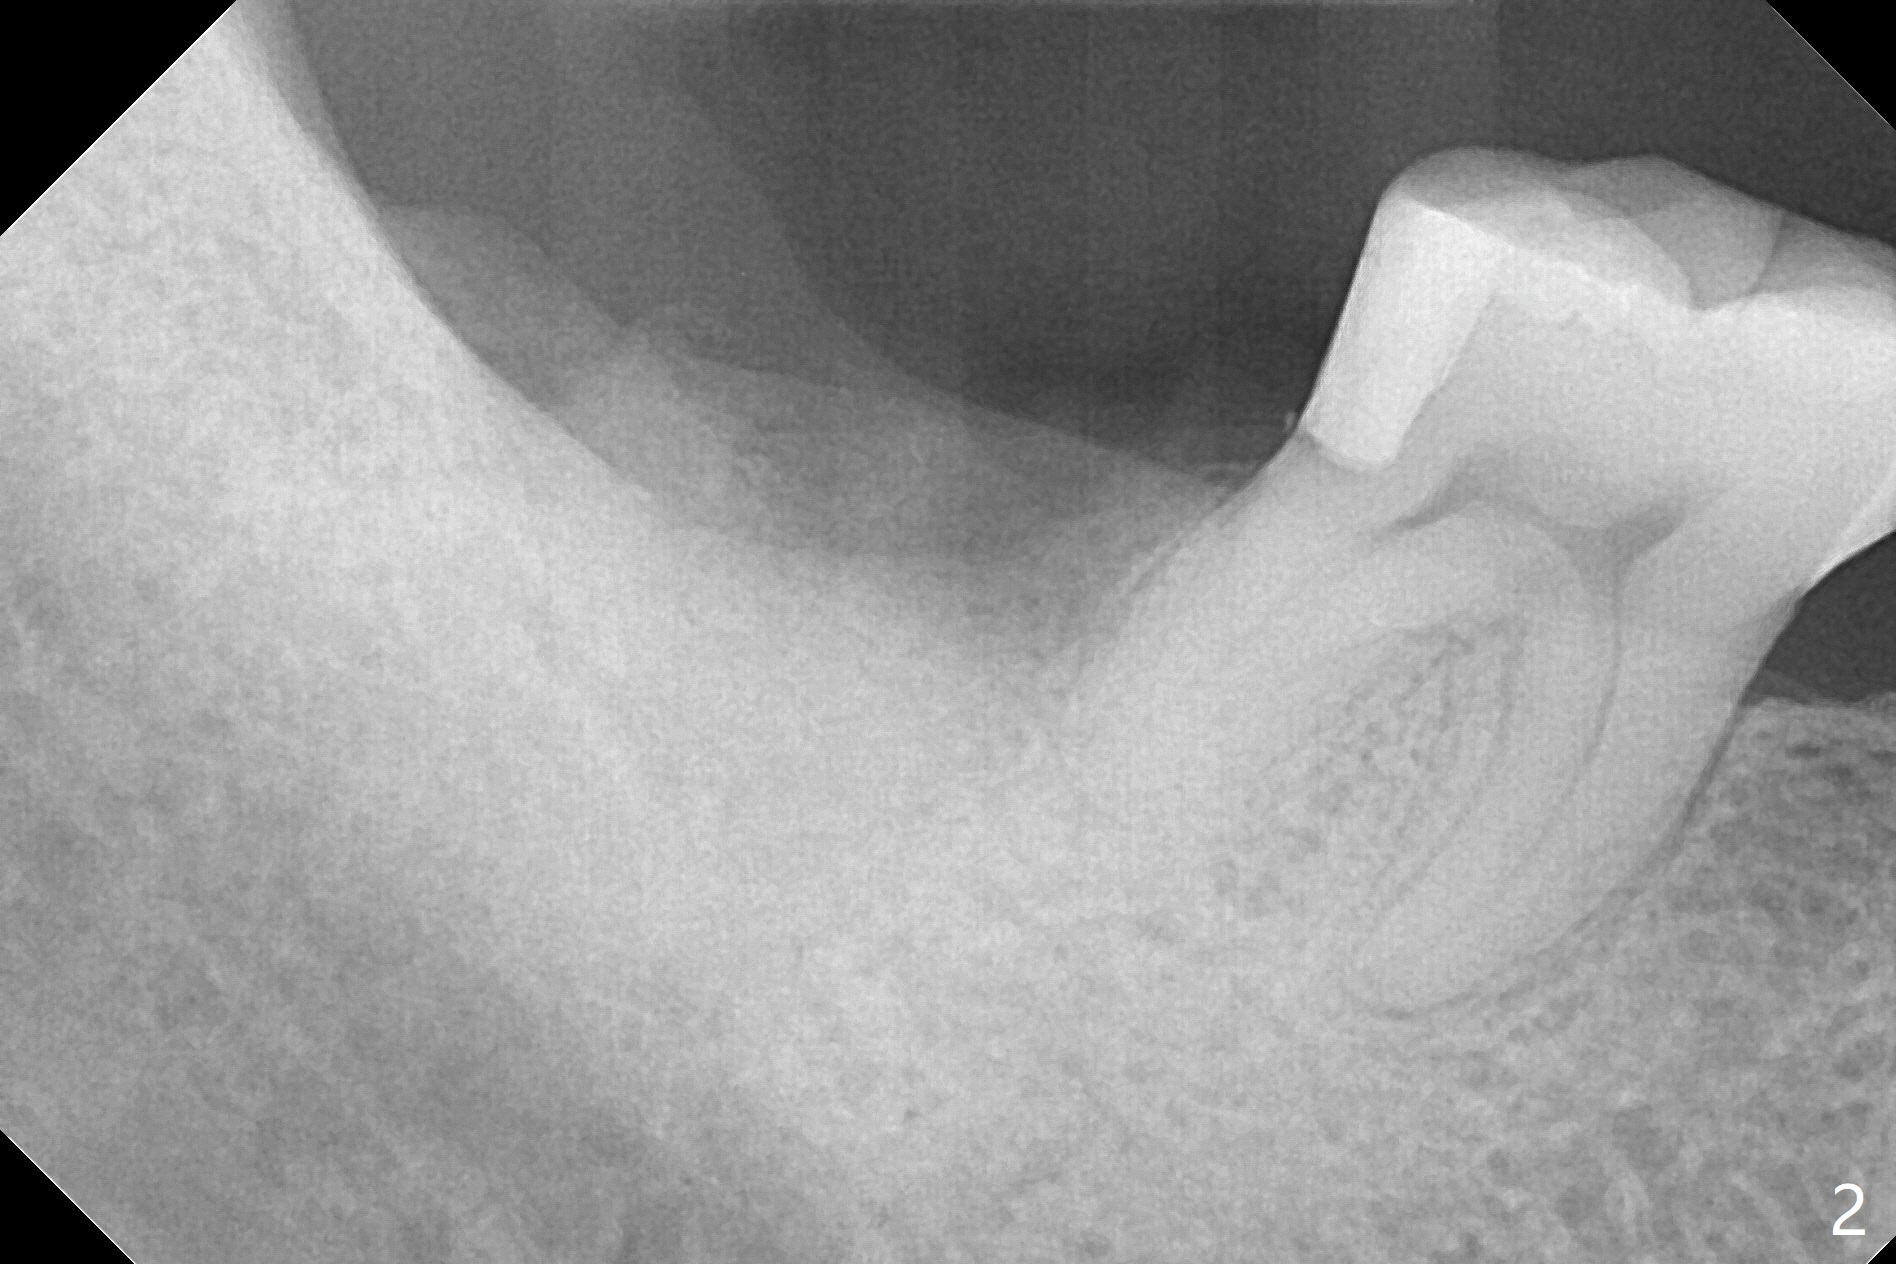

As expected, the buccodistal plate is low after extraction at #31. Osteotomy is initiated mesiolingually with 2 mm initial drill, 2.8 and 3.6 mm round drill with 4 mm stopper. The patient feels pain before the last drill reaches the depth. A 5x9 mm IBS dummy implant is placed with stability (Fig.1). When the definitive implant (5x9 mm) is placed, stability is lost. A 5.5x9 mm dummy implant achieves stability, while the definitive one loses stability. Increase in depth with 4.3 mm Magic Drill meets pain. Hemorrhage is another factor. When hemostasis is temporarily controlled, bone core is found. Nor removal of bone core with Final Drill or addition of allograft (Vera, .2-1.0 mm) in the osteotomy helps obtaining stability. Finally socket preservation is performed (Fig.2).